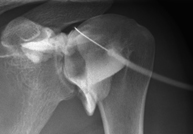

Tècnica que usa els raigs X a través de la qual s'obtenen imatges de l'interior de les extremitats per al seu estudi, especialment dels ossos. Indicacions: traumatisme, infeccions articulars. - RX Artrografia

Procediment que permet, mitjançant l'ús de raigs X, i després d'injectar un contrast a l'interior de l'articulació, detectar lesions d'aquestes articulacions (cartílag, os, tendons, etc. ) segons la distribució del contrast. - RX Pelvis